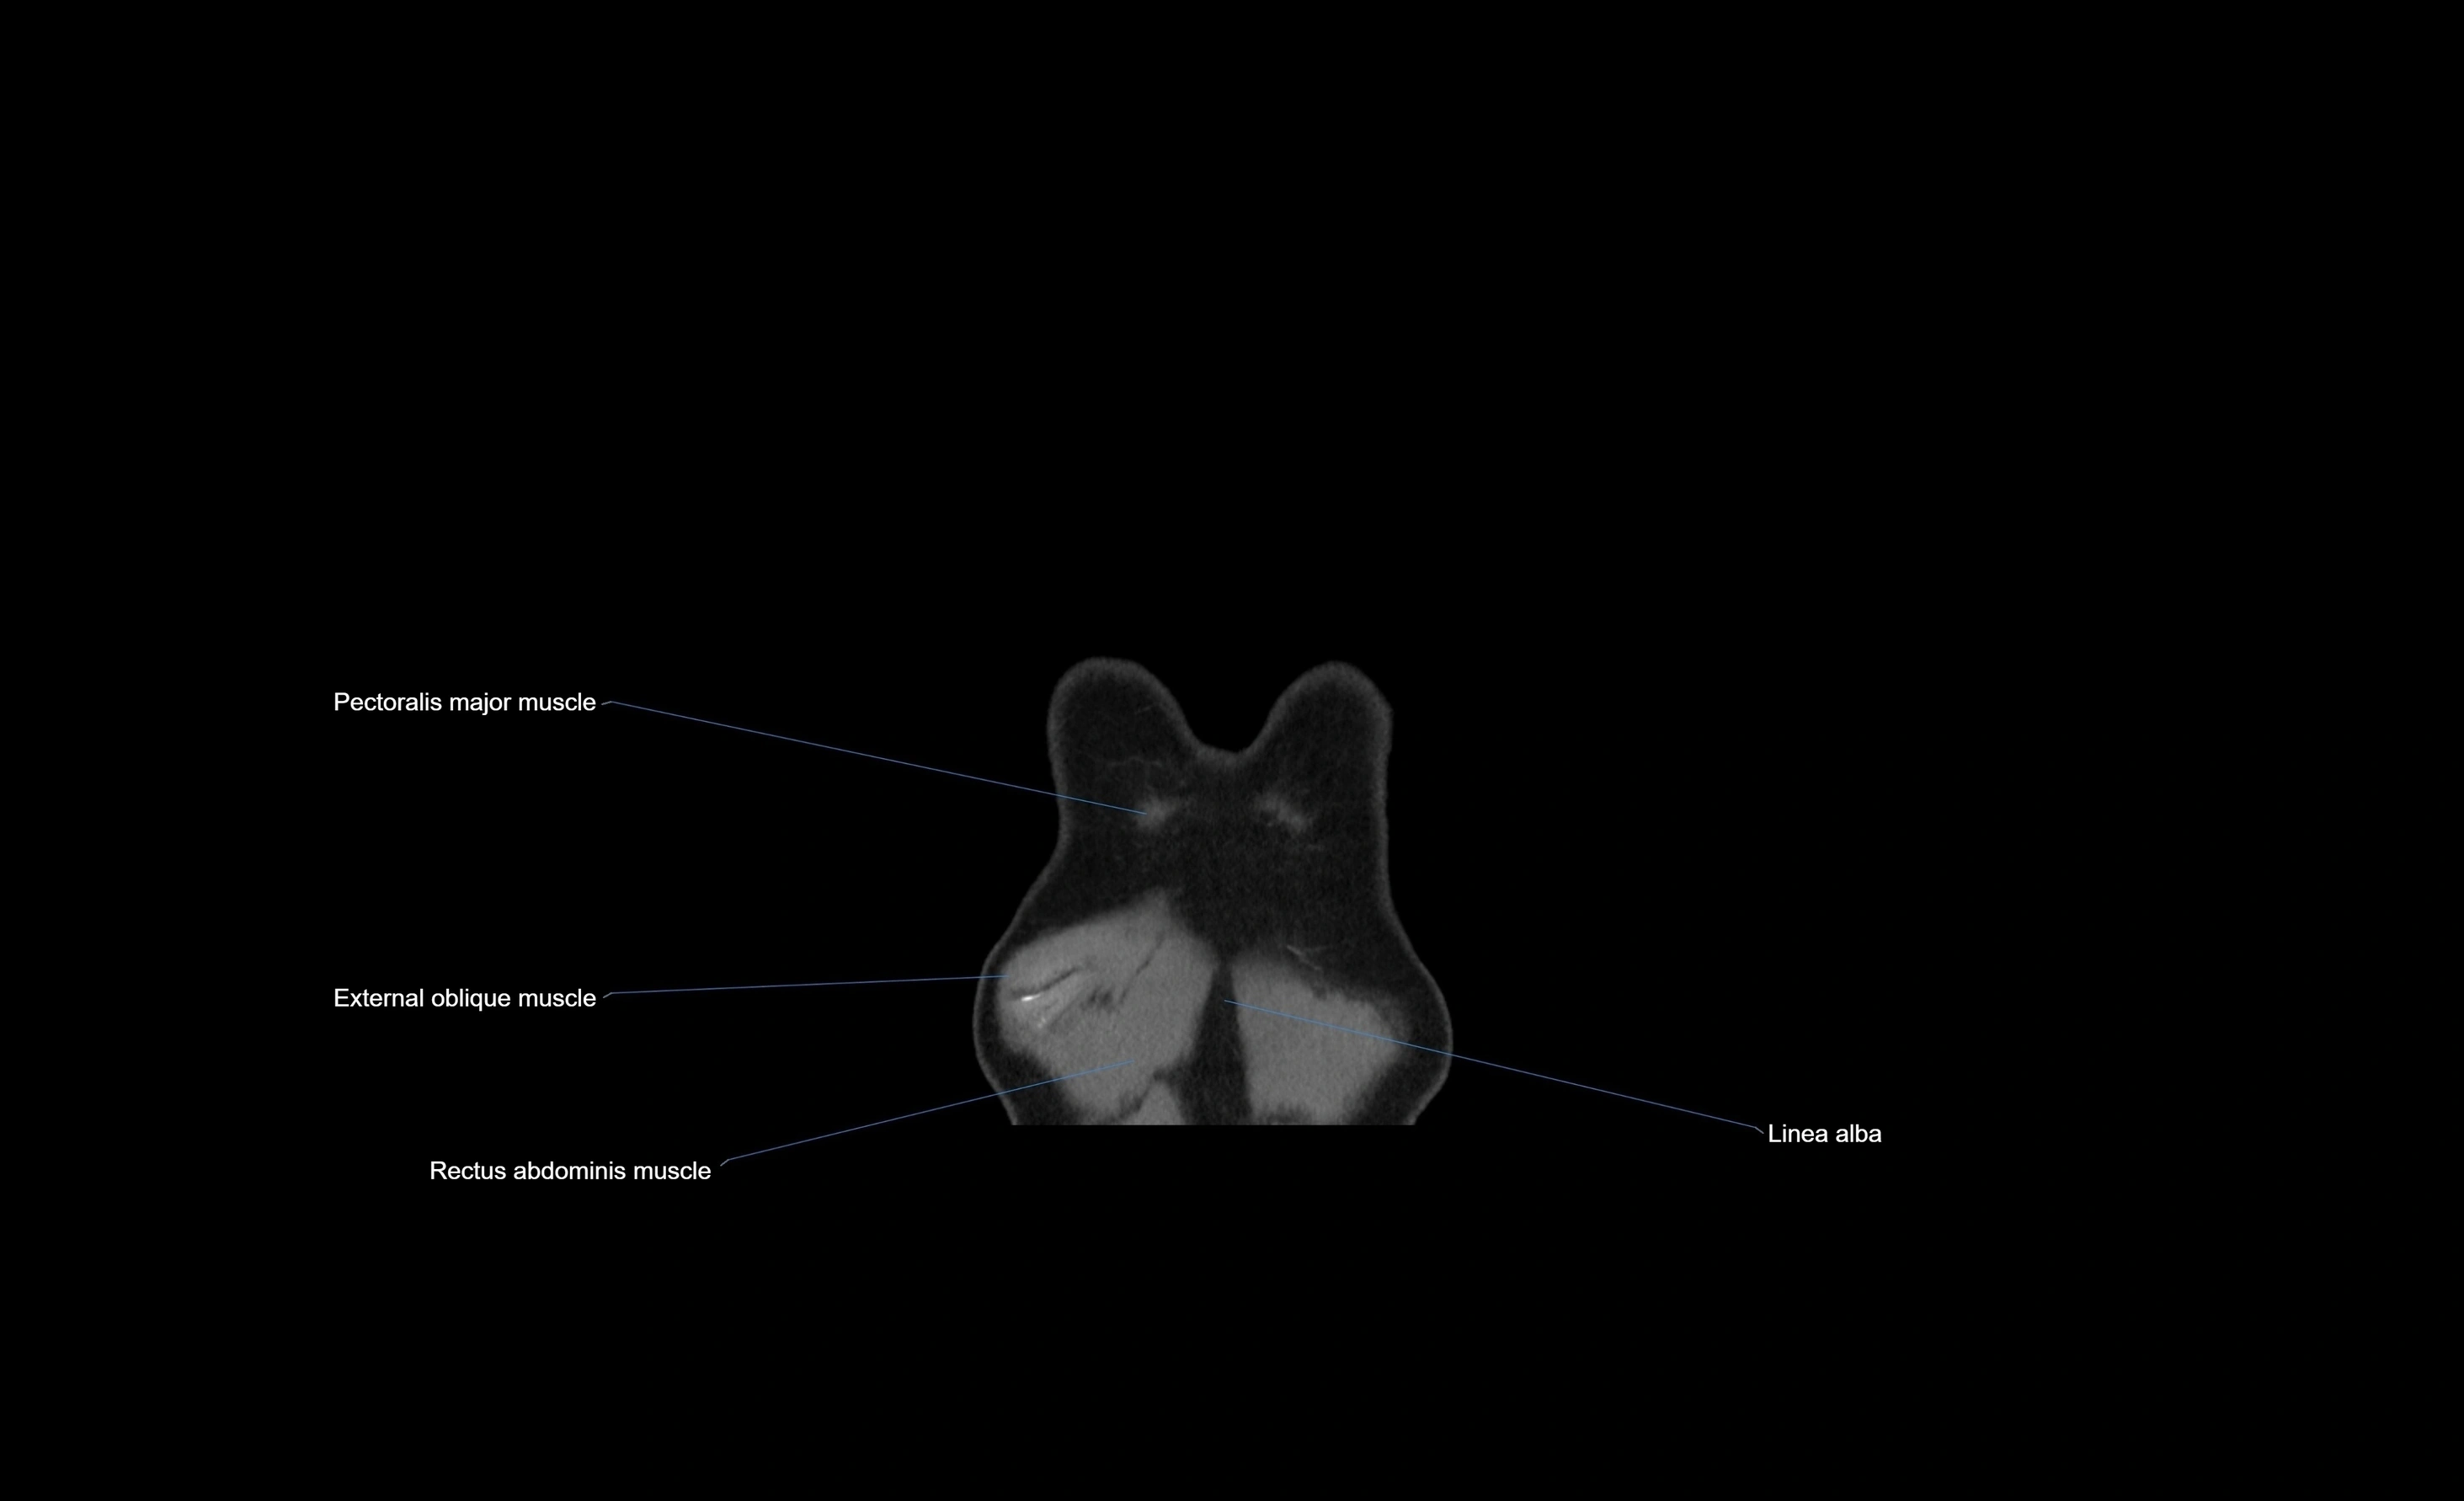

- External oblique muscle

- Pectoralis major muscle

- Rectus abdominis muscle